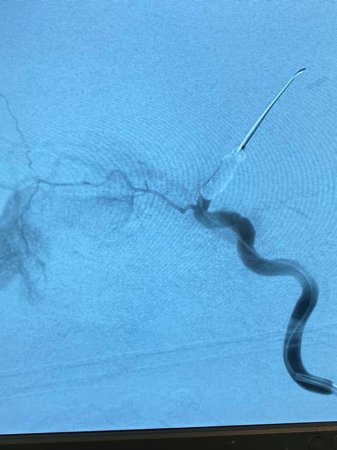

For the first time in Central Asia, the Scientific Center of Pediatrics and Children’s Surgery has launched a high-tech organ-preserving treatment of selective intra-arterial chemotherapy of retinoblastoma, which allows you to preserve the eye and even vision.

Annually in the Republic of Kazakhstan 20-25 new cases of retinoblastoma are detected. Since 2015, all patients with retinoblastoma have been treated at the Scientific Center of Pediatrics and Children’s Surgery. Together with the Kazakh Research Institute of Eye Diseases, the Center introduced such organ-preserving methods of treatment as laser transpupillary thermotherapy, intravitreal chemotherapy, cryodestruction, and now selective intra-arterial chemotherapy.

Selective intra-arterial chemotherapy for 15 years of use in the USA and European countries and 10 years of use in Russia has shown high efficiency, allows you to save the eye as an organ, and even vision. In the United States, over the years of use, the number of operations to remove the eyeball has decreased from 95% to 8%.

“The Center has all the conditions for carrying out operations - special medical equipment, apparatus and trained specialists. We have been going for this day for 5 years. This is a unique event for us and for parents. For the first time in Kazakhstan, an organ-preserving operation SIACHT has been started. In November 2016, an application was submitted for consideration of a new SIACHT technology for retinoblastoma. Due to the pandemic, the clinical protocol was approved only on August 25, 2021. During this time, we conducted 2 master classes, 12 children were operated on, ”said ophthalmologist Elena Tyan.